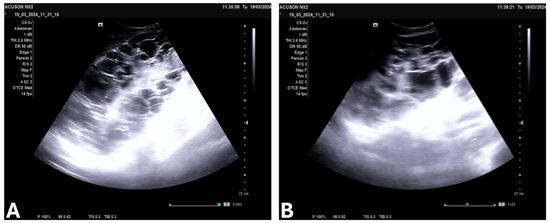

2. Materials and Methods

3.4. Laboratory Findings, Imaging, and Stage of ADPKD